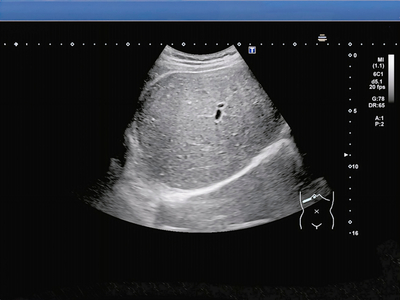

手機收購急診醫師魏智偉在《健康零距離》指出,自己遇過一名令他印象深刻的15歲高中生病患,外觀有些肥胖,因肚子劇烈疼痛送急診,檢查後確診急性胃炎,期間做超音波時更發現,他的肝「整塊白白亮亮」,有脂肪肝的問題,程度已經不是輕度。患者坦言自己每天放學後補習,都不是吃有菜有肉的便當,而是雞排配珍奶。